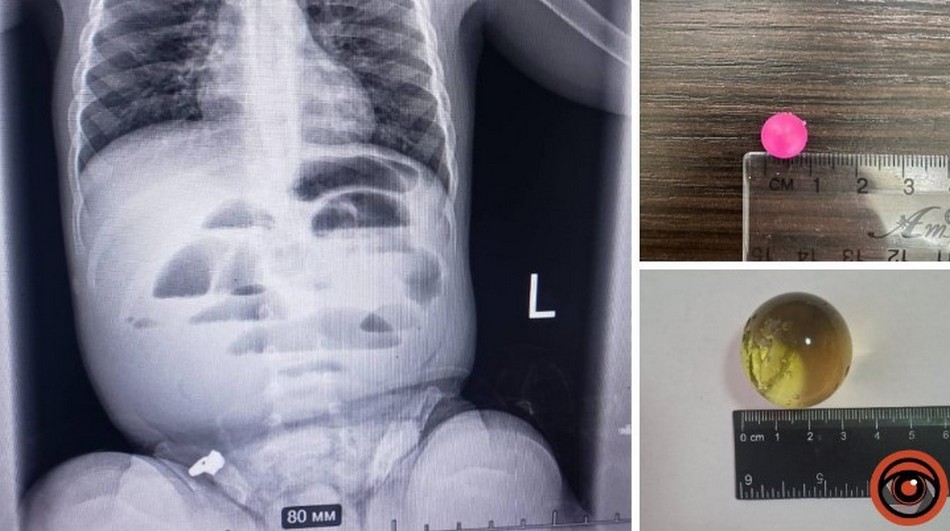

У Дніпрі дитина віком 1 рік і 8 місяців проковтнула гідрогелеву кульку. Її доставили до лікарні з підозрою на кишкову непрохідність. Медики зробили рентген і побачили, що кишківник заблокований. Під час операції виявили, що кулька всередині розрослася до трьох сантиметрів і перекрила шлях їжі.

Лікарі вчасно дістали кульку та наклали шви. Дитину перевели до реанімації. Медики нагадують батькам: такі кульки небезпечні, бо можуть рости всередині організму.